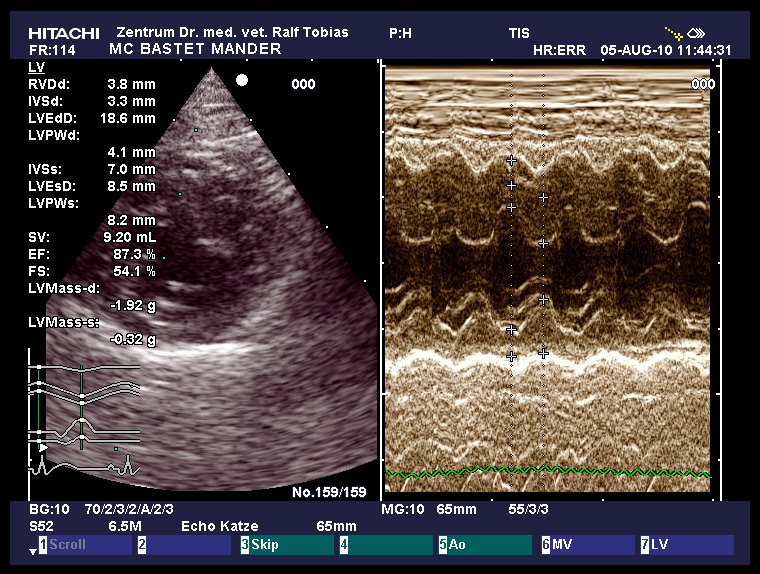

HCM-Schall August 2010

|

HCM normal

other diagnosis:

ggr. Mitralklappeninsuffizienz

age: 6y 7m

weight: 5.25 kg

IVSd: 3.3 mm

LVFWd: 4.1 mm

SAM: no

papillary muscles: normal

Dr.Tobias, Hannover